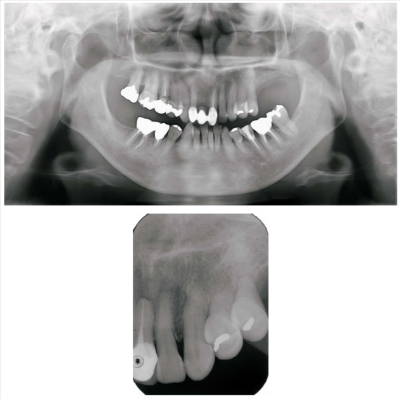

53 歳の女性。上顎左側犬歯部歯肉の腫瘤を主訴として来院した。6か月前から徐々に大きくなったという。疼痛はない。初診時の口腔内写真とエックス線画像を別に示す。

適切な処置はどれか。1つ選べ。

d. 生検